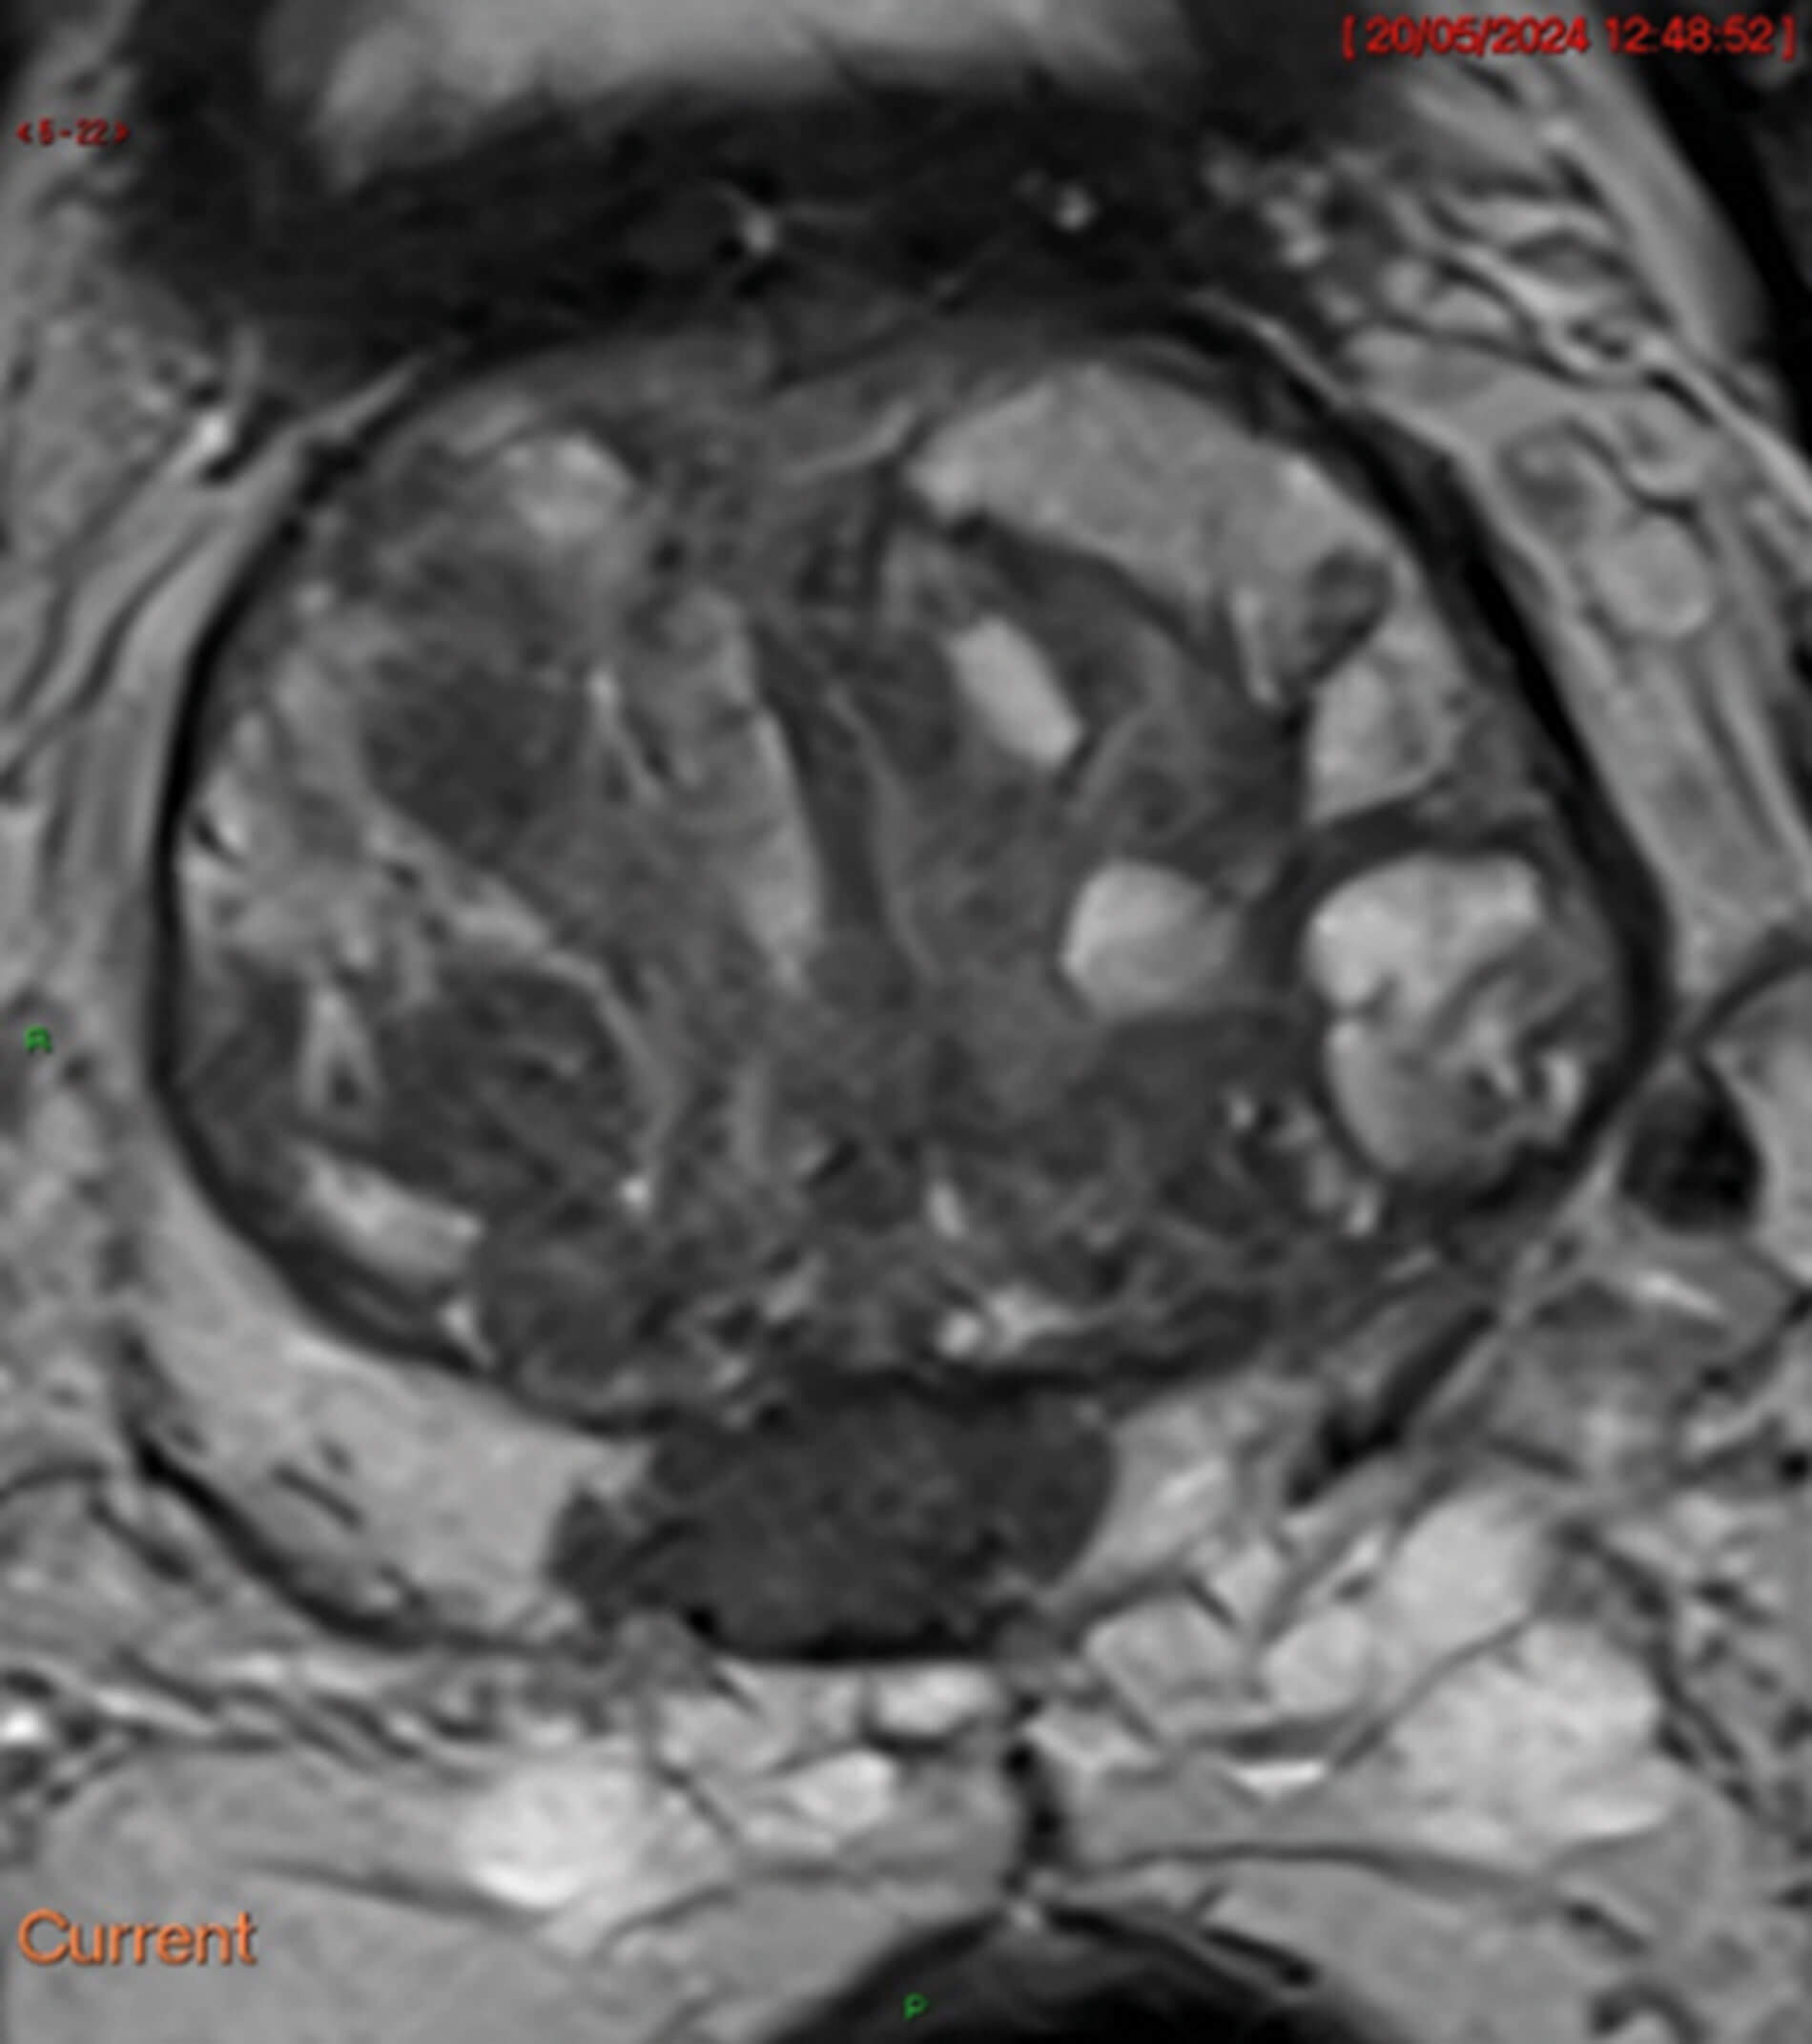

Figure 1.

- Figure 1 is a T2 weighted MRI image. What does it show?

2. On this T2 weighted image, there is a 2cm mid-gland lesion at 6 o’clock in the peripheral zone. It is stage T2aN0Mx. On T2 weighted images, prostate cancer usually appears dark. In the transition zone, T2W imaging takes precedent when interpreting the images for cancer.